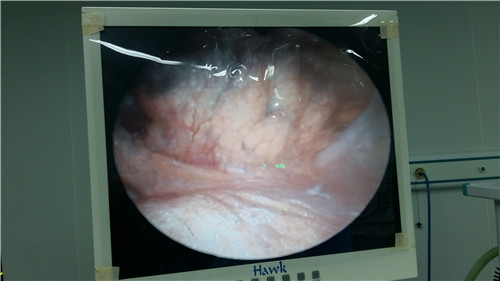

网站首页 » 科室介绍 » 脊柱科 » 腰椎间盘突出 » 病因